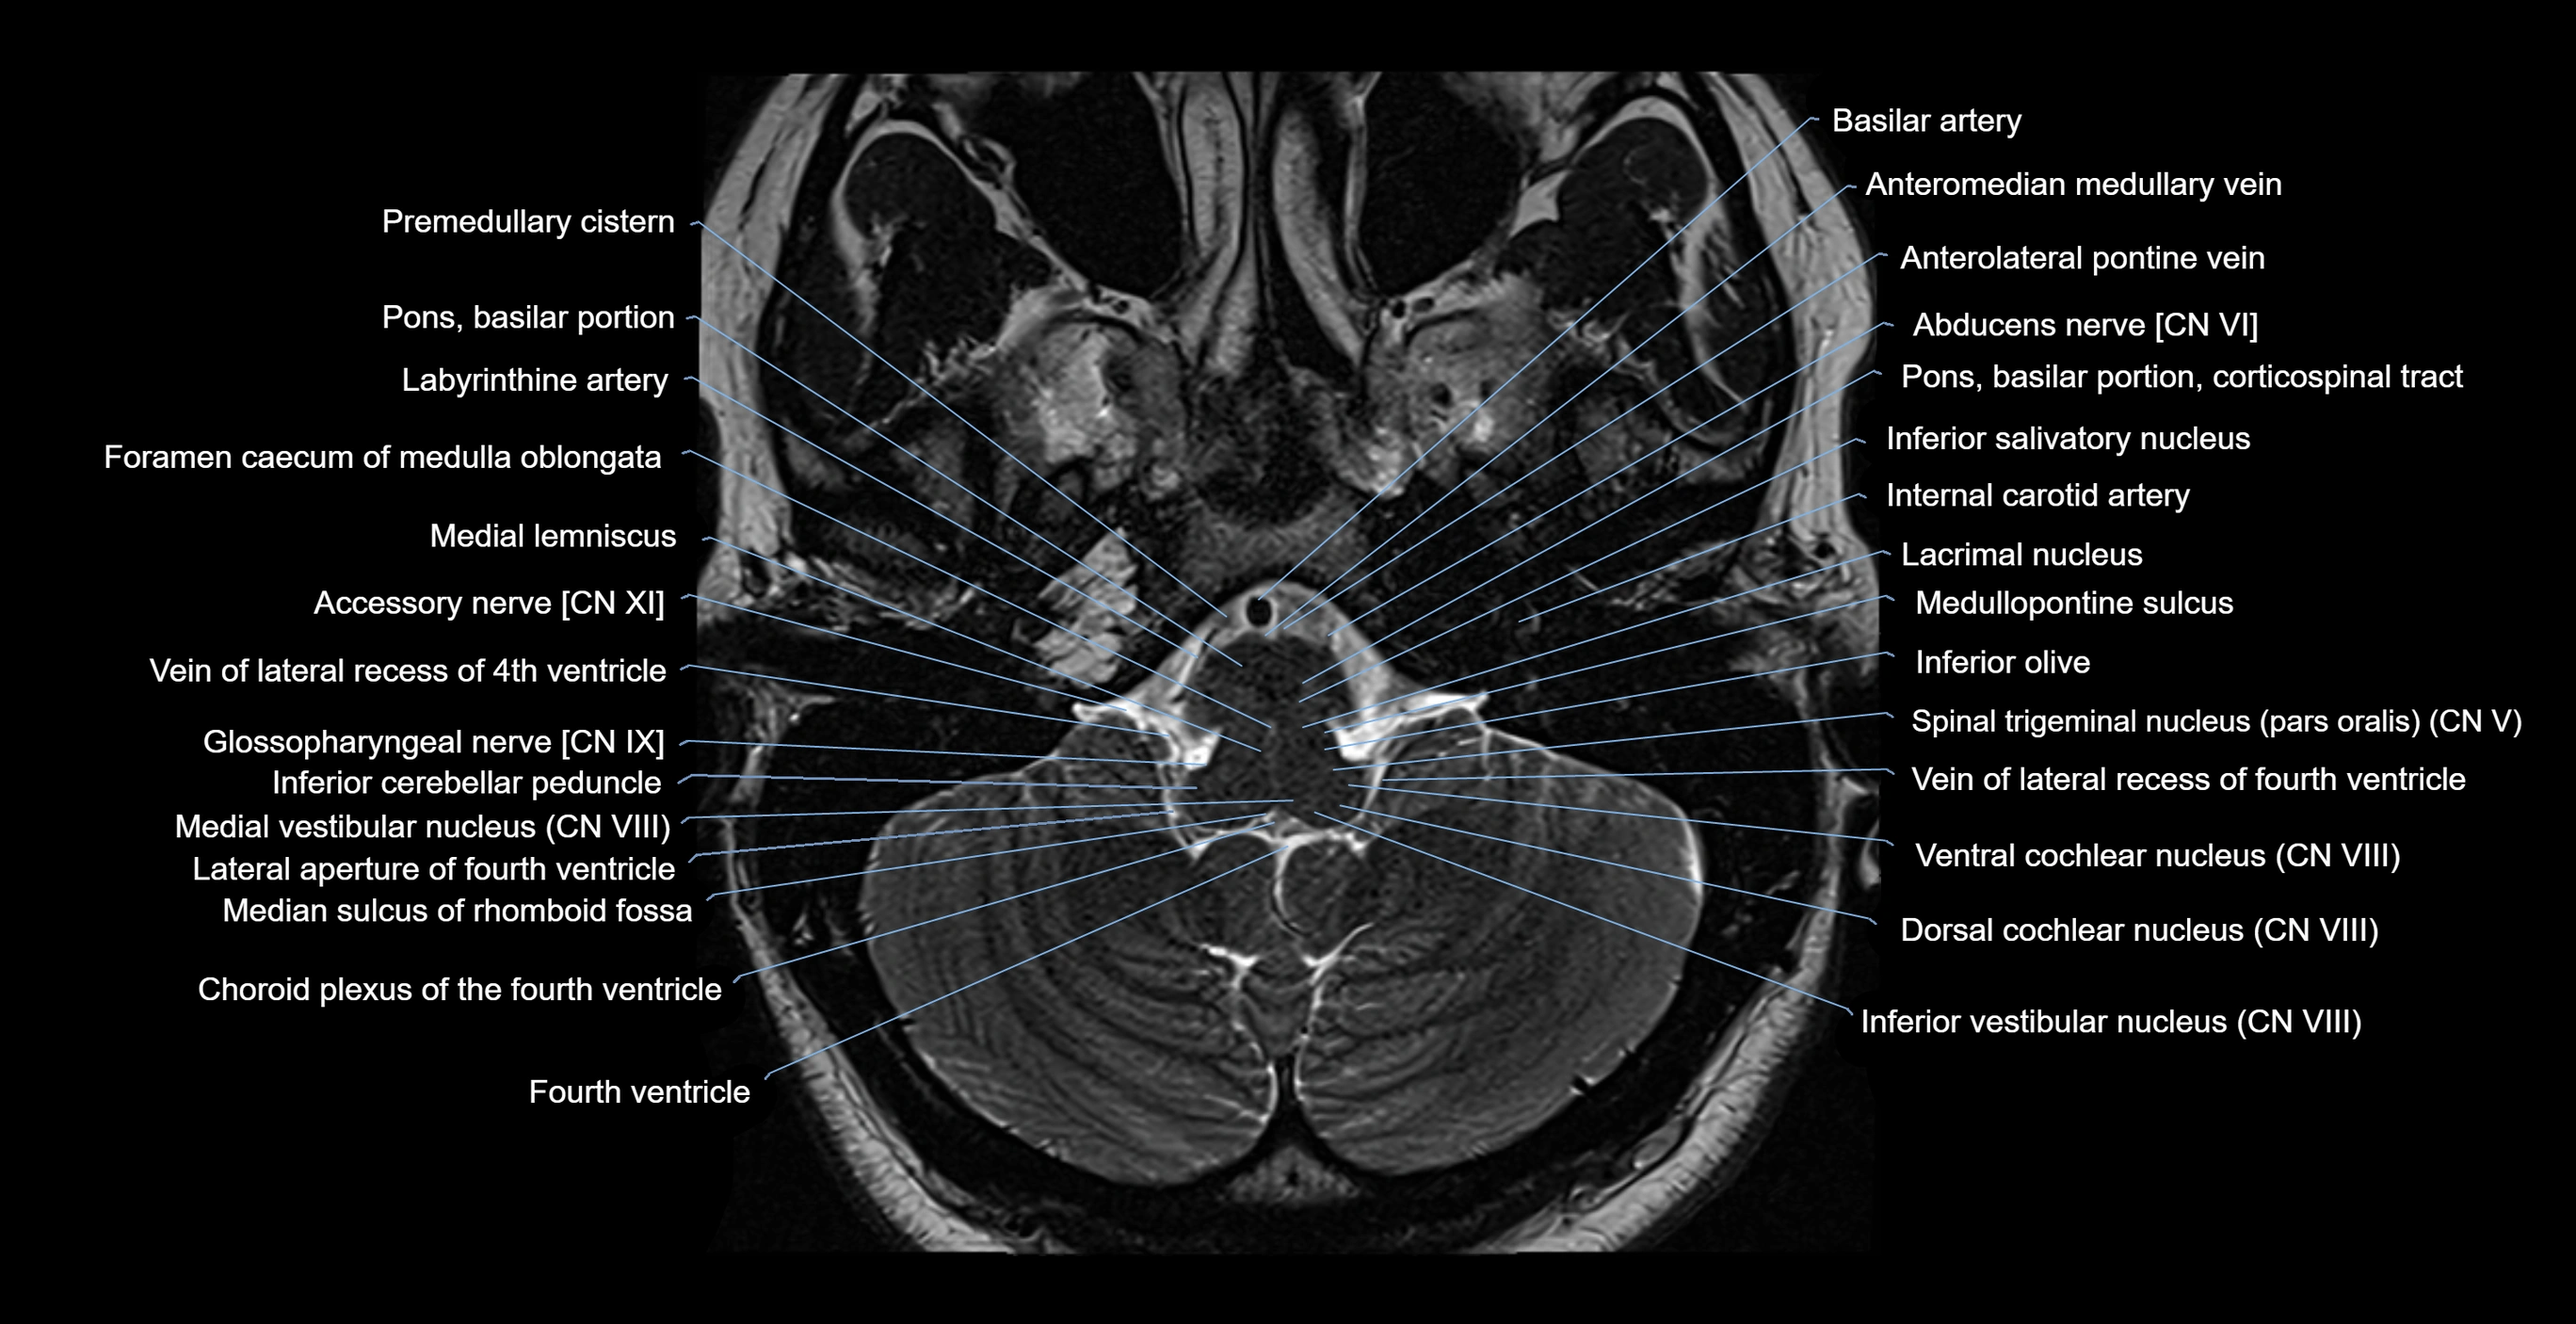

MRI images